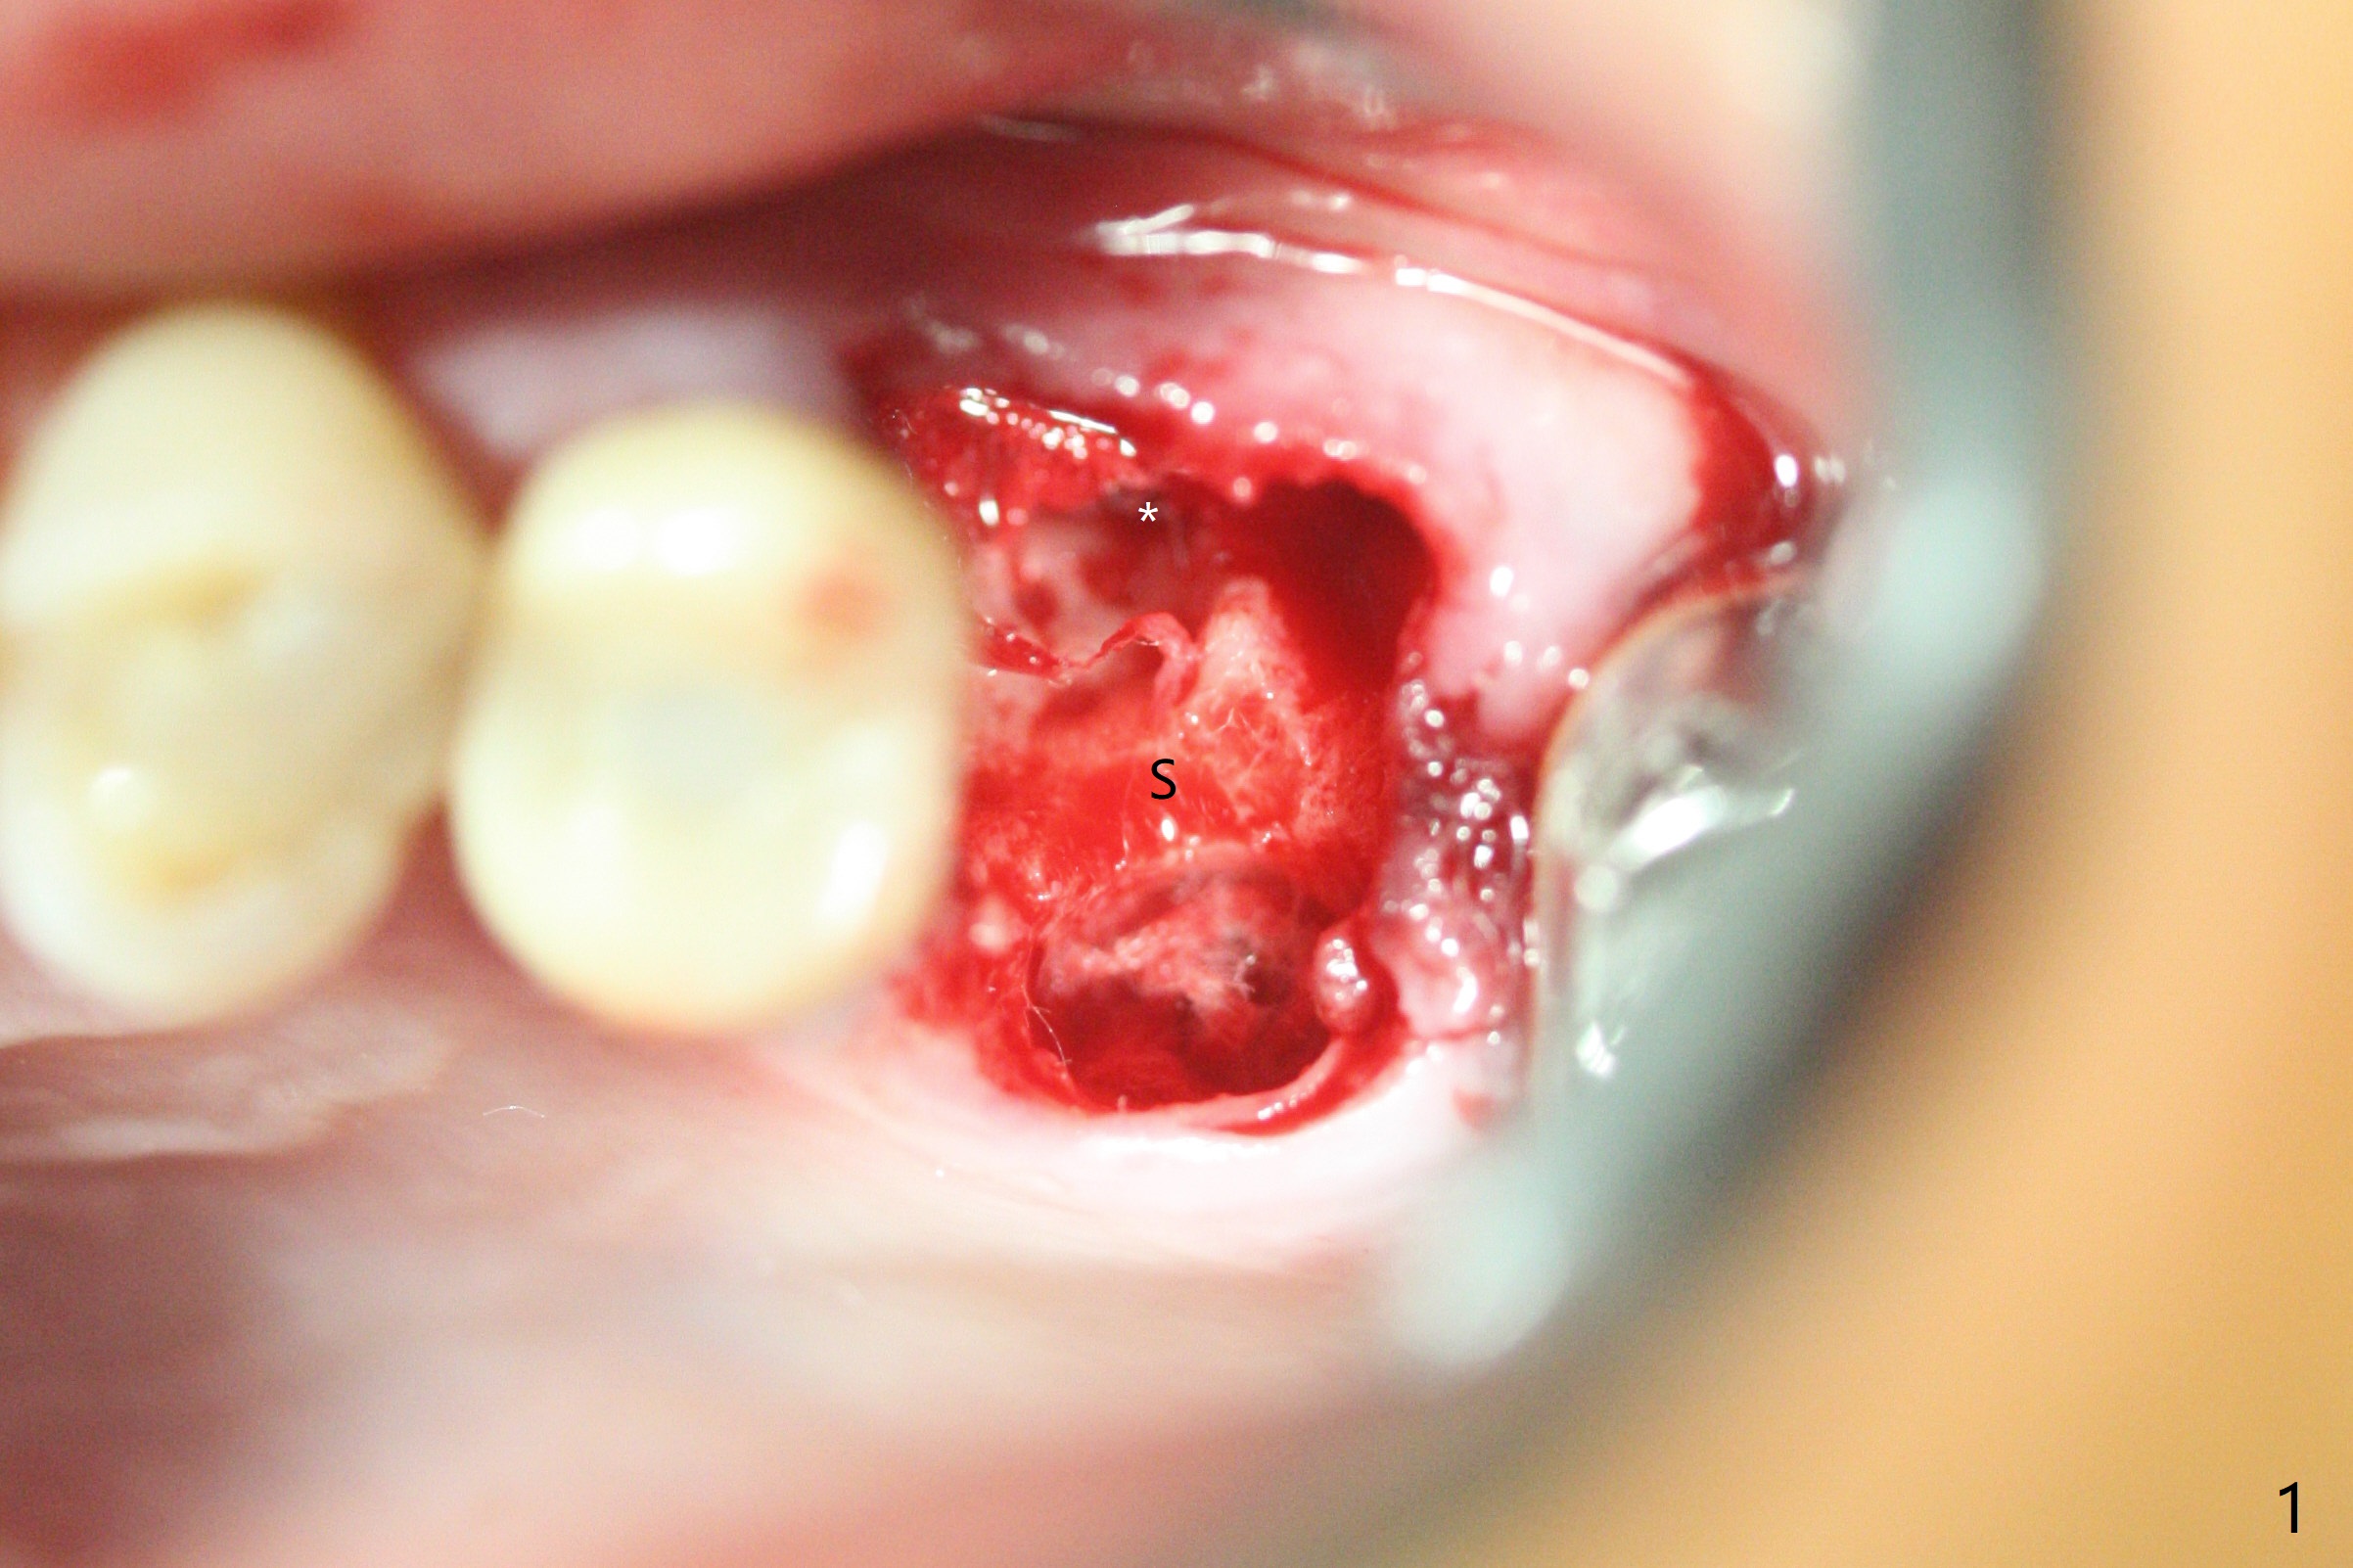

左上六拔除后,近中颊侧窝尤其大,与上颌窦相通(图一 *),而中隔比较尖,截除后还显得窄(图一,二:S),不太适合即刻种植。放置一块PRF膜于近中颊侧窝修补上颌窦,然后放置粘性骨块,好像有上颌窦提升迹象(图三:*(箭头:近中颊侧骨板缺失)),用骨粉填满其余牙槽窝(图四),覆盖另外一块PRF膜以及Cytoplast(不可吸收膜),用PTFE缝线(也不可吸收,与膜是同一个材料,非常柔软,好打结)缝合(图五)。最后使用牙周敷料。后者术后八九天脱落,病人术后十二天复诊,不可吸收膜腭侧有些外翻(图六箭头),伤口愈合尚可,没有骨粉丢失迹象,反复交代口腔卫生。再过三周撤除不可吸收膜。其实三周后膜自己脱落,病人回来撤去剩余缝线(图七),新鲜肉芽组织形成。术后5个月牙槽嵴和角化龈宽,骨高度尚可(图八),密度差些(图九,750单位),植体应该是4.5x8.5 或者 10 毫米,少量上颌窦提升。